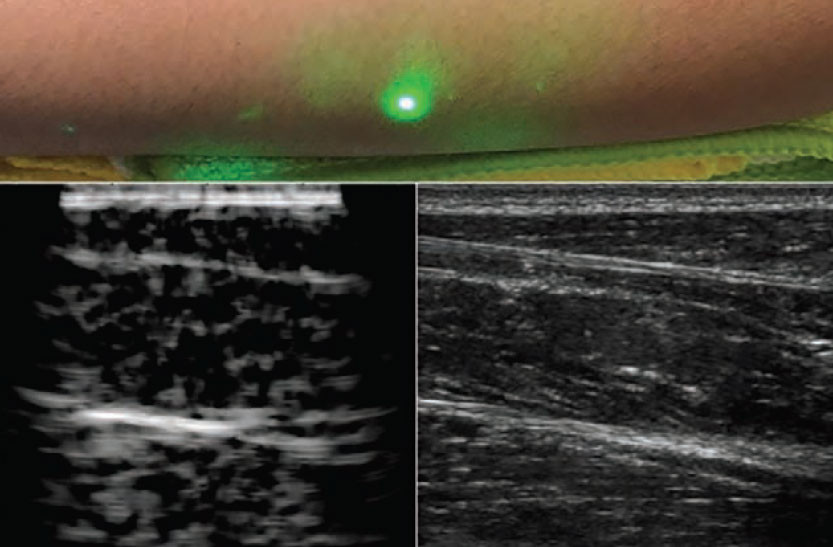

Metoda e re ka zbuluar se laseri, i cili pulson në një gjatësi valore prej 1.550 nanometrash, mund të gjenerojë valë të zërit kur e godet lëkurën e njeriut. Një laser i dytë, i cili e gjurmon të njëjtën gjatësi valore, mund t’i detektojë më pas valët e reflektuara zanore dhe ta gjenerojë një fotografi të ngjashme me atë të një ultrazëri konvencional.

Në studimin e ri, hulumtuesit e demonstrojnë zhvillimin e suksesshëm të kësaj teknike të re me ultrazë laserik, nga testet fillestare në një model xhelatine që i ngjan lëkurës së njeriut, e deri tek indet e prera shtazore. Studimi përfundimisht e tregon efikasitetin e metodës në vullnetarët njerëzorë, duke i paraqitur imazhet e para me ultrazë laserik pa kontakt me parakrahun e njeriut.

Në këtë pikë metoda nuk jep imazhe në rezolucione të barabarta me teknikat konvencionale të ultrazërit, megjithatë, studiuesit sugjerojnë se ky është vetëm momenti i parë zhvillimor që duhet kapërcyer. Sistemi potencialisht mund të rafinohet dhe përmirësohet për të dhënë detaje më të imëta të indeve.